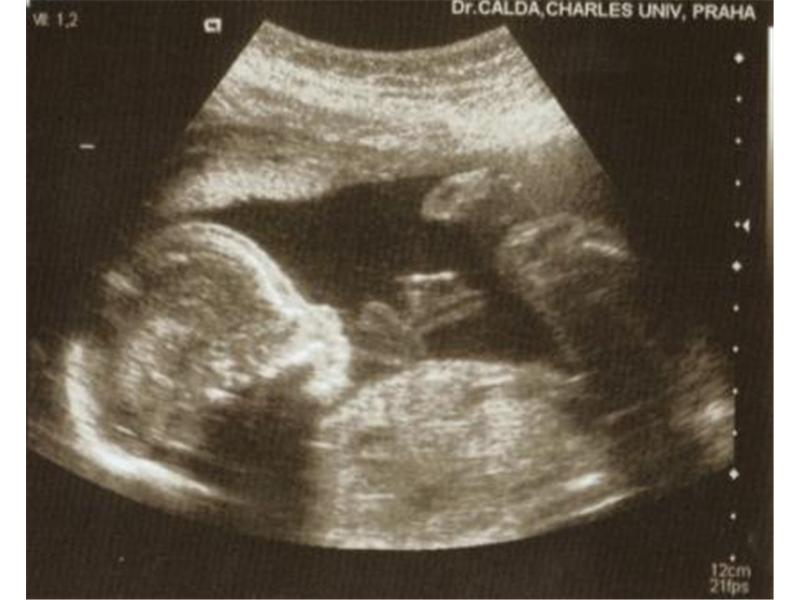

Zdroj: archiv redakce